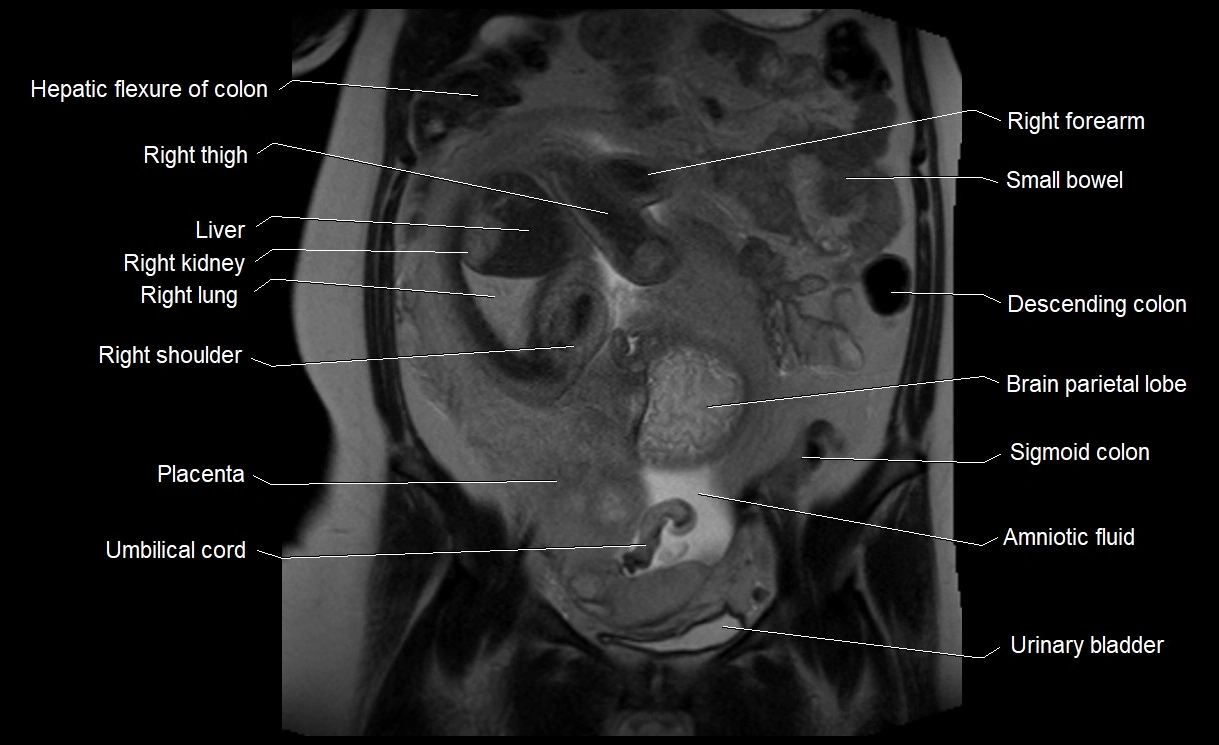

MRI Appearance

T2 HASTE (T2 GRE):

• Amniotic fluid shows very bright hyperintense signal

• Provides natural contrast against fetus and placenta

• Small particles (vernix) may appear as scattered hypointense foci within bright fluid

T1 GRE:

• Amniotic fluid shows low signal intensity (dark)

• Hemorrhage, infection, or proteinaceous content may cause focal or diffuse high signal intensity